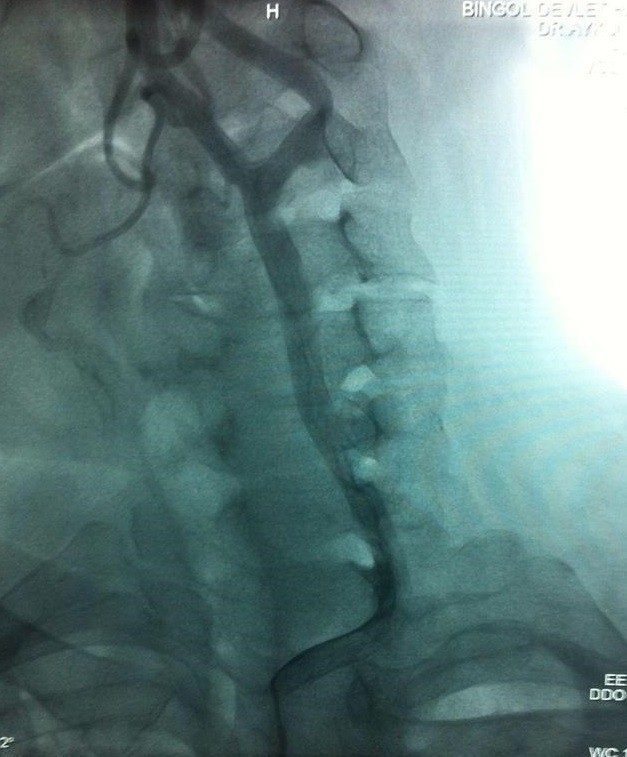

Bingöl’de İlk Defa Şah Damarı Anjiyografisi

Bingöl'de ilk defa karotis (şah damarı) anjiyografisinin gerçekleştirildiği bildirildi.

İl Sağlık Müdürlüğü tarafından yapılan açıklamada, Devlet Hastanesi Anjiyografi Laboratuvarında bir ilk olarak şah damarı anjiyografisinin başarılı bir şekilde gerçekleştirildiği aktarıldı.

Açıklamada," Karotis damar tıkanıklıkları, ülkemizde ve dünyada inmenin en önemli sebeplerinden birisidir. Hipertansiyon, diyabet, kolesterol yüksekliği ve sigara damarların tıkanmasında başlıca sebeplerdir. Bu tür hastalara anjiyografi yapılarak damar tıkanıklığının saptanması ve uygun olan hastalarda da stent takılarak tedavi edilmesi inmeden korumada modern, etkili bir tedavi yöntemidir. Son bir yılda 605, açıldığı günden bugüne toplam bin 621 anjiyonun yapıldığı Bingöl Devlet Hastanesi Anjiyografi Laboratuvarı, 7/24 saat hizmet vermektedir. Anjiyografi Laboratuvarının açılmasıyla birlikte il dışı sevklerde önemli azalmalar olmuş, vatandaşlarımıza ilimizde hizmet verilmeye başlanmıştır"denildi.